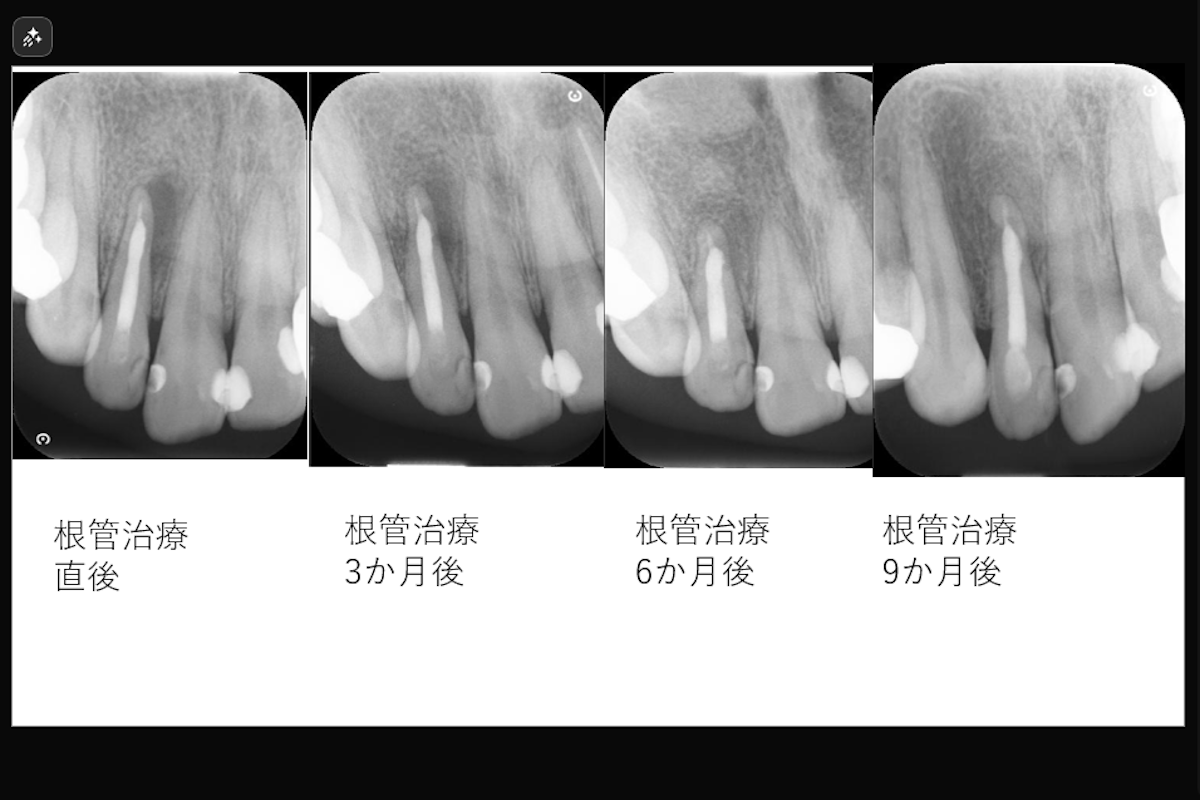

- 治療期間: 約1.5か月

- 治療回数2回

- 治療内容: 上顎右側側切歯 根管治療(レーザーを用いた根管洗浄、MTAを用いた根管充填)

- 治療のリスク: 残存歯質の厚みによって歯根破折のリスク、経過によっては外科的歯内療法